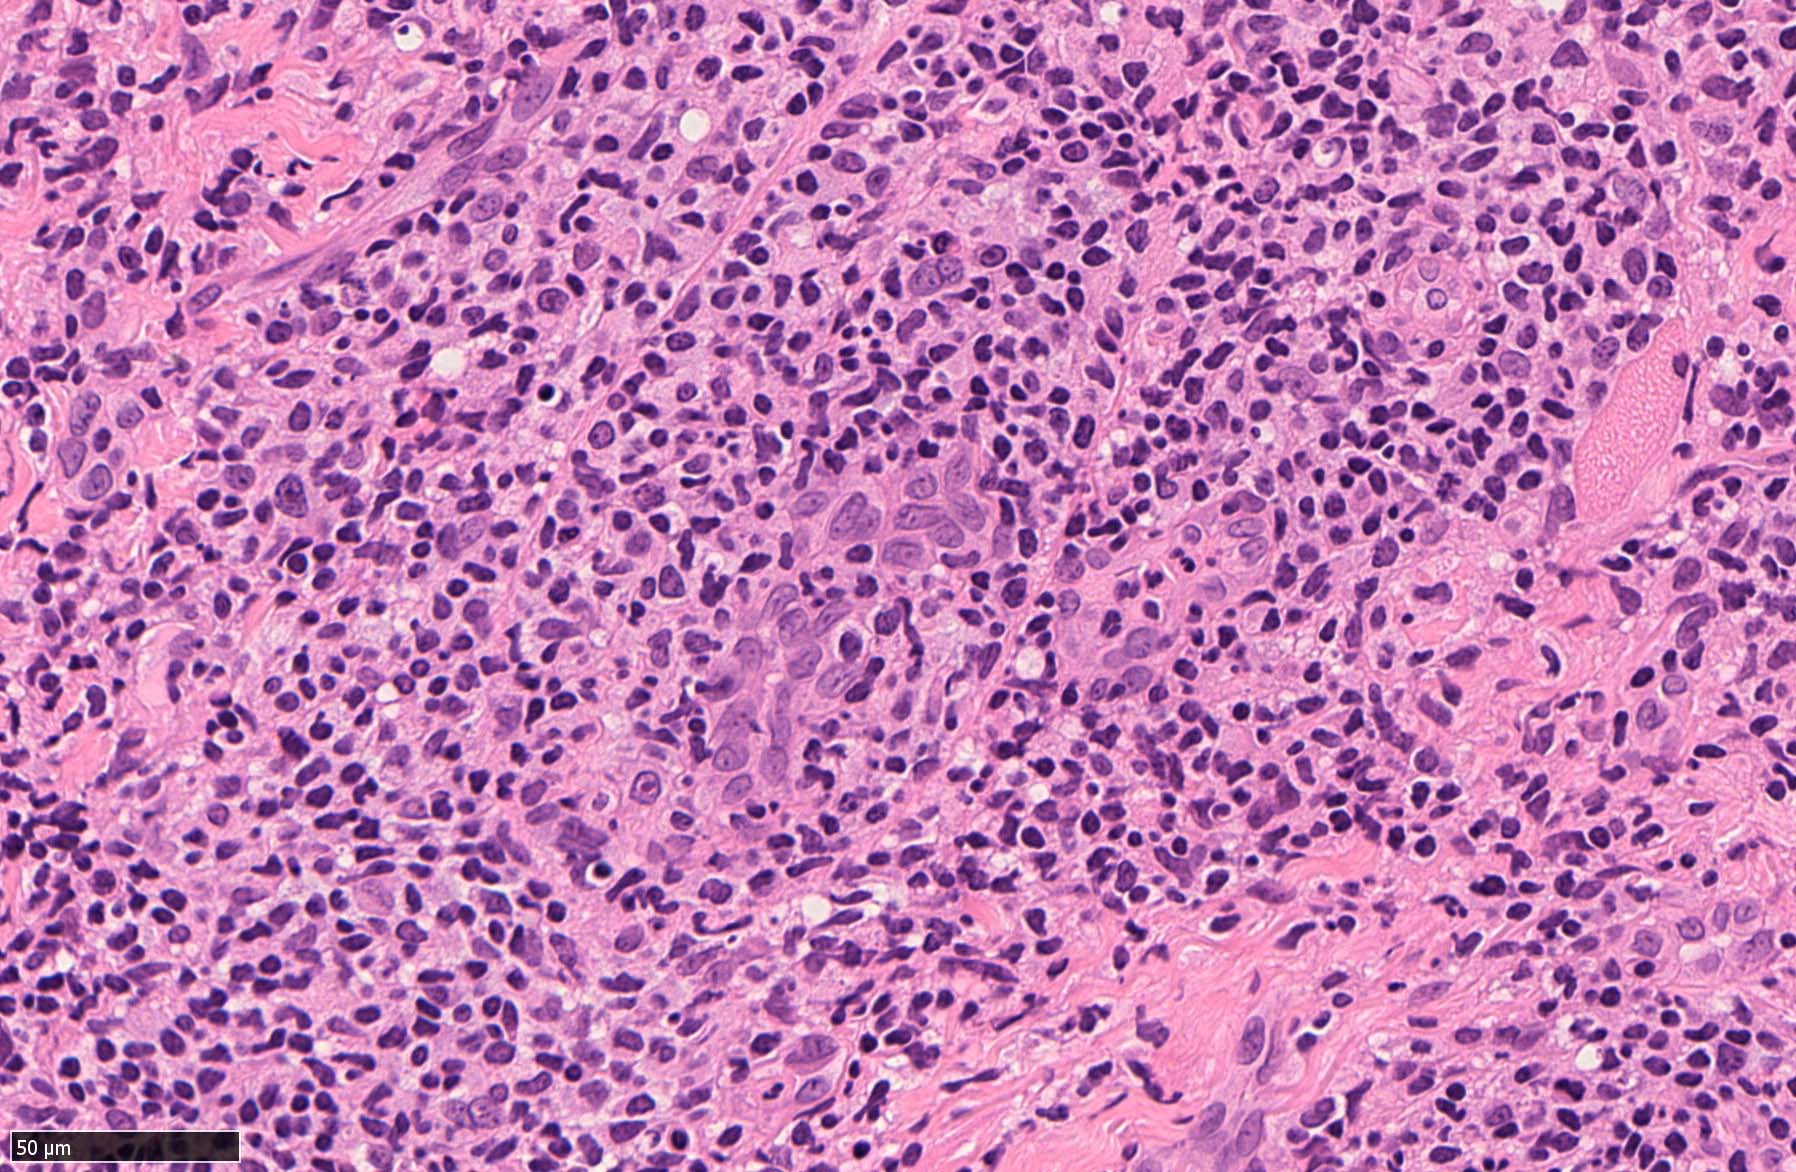

EBV陽性粘膜皮膚潰瘍(EBVMCU)は、EBV陽性の異型大型B細胞および/またはHodgkin/ Reed-Sternberg (HRS)様細胞を含む多形リンパ球浸潤を伴うリンパ増殖性疾患(pleomorphic pattern)で、

典型的には免疫不全/調節障害を有する患者の粘膜および皮膚に発現する。--WHO 5th classificationに記述された定義